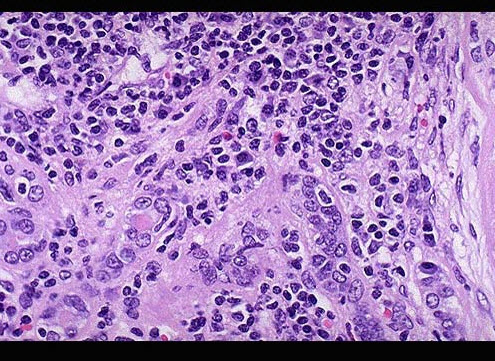

[单选题]女性,58岁,绝经后阴道不规则出血,行子宫切除手术,显微镜下见腺体结构少,实性巢状区占肿瘤部分70%,细胞异型性明显,核分裂像易见(如图)。应诊断为()A .子宫内膜腺癌Ⅰ级B .子宫内膜腺癌Ⅱ级C .子宫内膜腺癌Ⅲ级D .子宫内膜间质癌肉瘤E .子宫内膜腺肌瘤